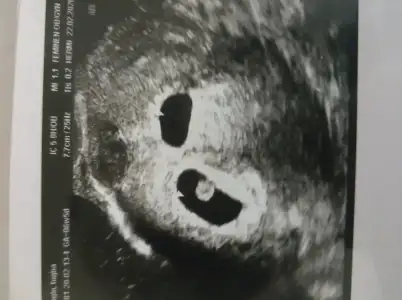

Önümüzdeki hafta hepimiz güzel haberlerle doldururuz burayı inşallah. Benim yarın sabah kalp sesini dinlemek için randevum var ama kalp sesinin yanında kanama alanı azalmıştır inşallah diyorum